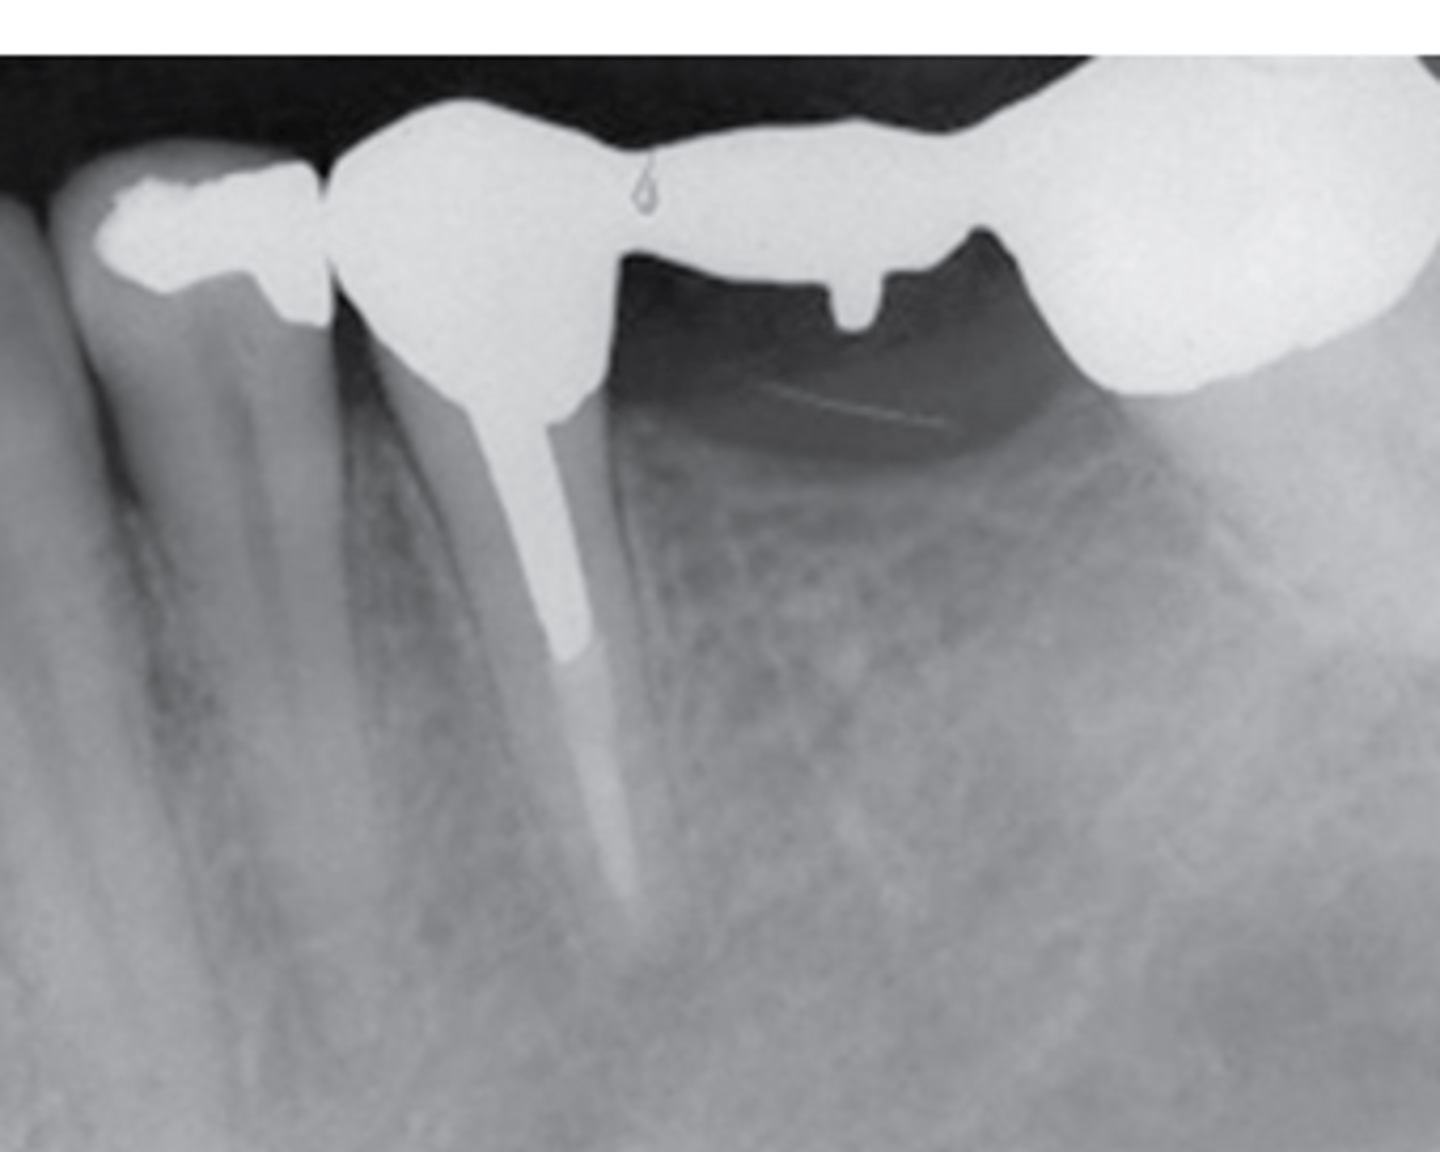

what is used to fill root canals?

gutta percha (zinc oxide)

radiopaque

gold crown

gold crown with post

crown prep

porcelain fused to metal radiograph

porcelain fused to metal image